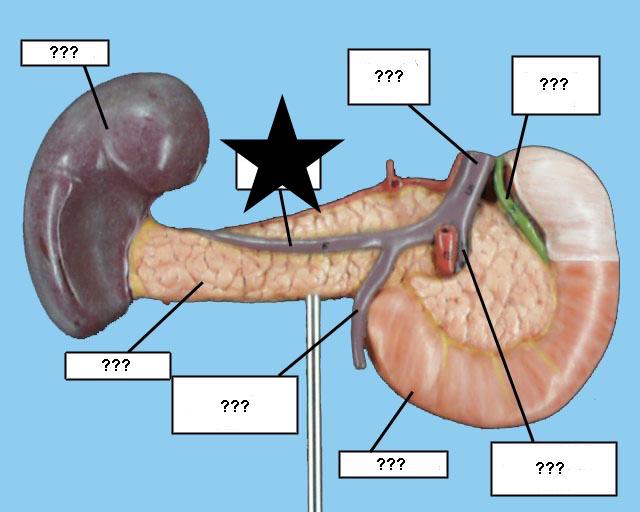

(Common) Hepatic Duct

Common bile duct

Common hepatic artery

Cystic duct

Duodenum

Gall bladder

Hepatic portal vein

Kidney

Liver

Pancreas

Pancreatic duct

Splenic artery/vein

Stomach